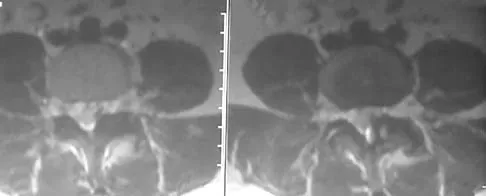

A 42-year-old woman underwent an instrumented posterior spinal fusion at L3-S1 with transforaminal lumbar interbody fusion. She had an excellent clinical result with complete resolution of leg pain. Three months later she now reports increasing back pain and weakness in her legs. Examination reveals weakness in the quadriceps and tibialis anterior. Radiographs show no interval changes in the position of the hardware. MRI scans are shown in Figures 2a through 2c. What is the next most appropriate step in management?

Explanation